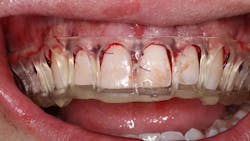

The new digital approach (figures 2–13) to an osseous crown lengthening procedure involves photographs, radiographs, intraoral scans, and CBCT data for a facially driven treatment plan. This approach starts with the end result in mind and ultimately requires fewer appointments for the patient. It also leads to more predictable esthetic results.

Once the patient accepts treatment and is on board for the crown lengthening as proposed, a surgical guide stent must be created and printed for approximation of the new crown margins. Using the smile creator Exocad, a digital mock-up of the final margins of the newly lengthened teeth is generated. The patient can be presented with the simulated smile and accept the look of the mock-up before digitally fabricating the surgical guide needed to achieve said results.

Utilizing a facially driven treatment plan, the facial photographs were merged with the CBCT scan to assess bone levels, and the central incisors were digitally planned to exhibit a new length of 11.5 mm, to enhance the patient’s long facial structure. The new width of the veneers could then be generated to be 85% of this measurement to achieve the golden proportion for optimal esthetics. Once the surgical guide is designed in Exocad to achieve these coronal margins, the guide design is exported to SprintRay to be printed with a snug fit for accurate coronal margination for the final restorations later on.